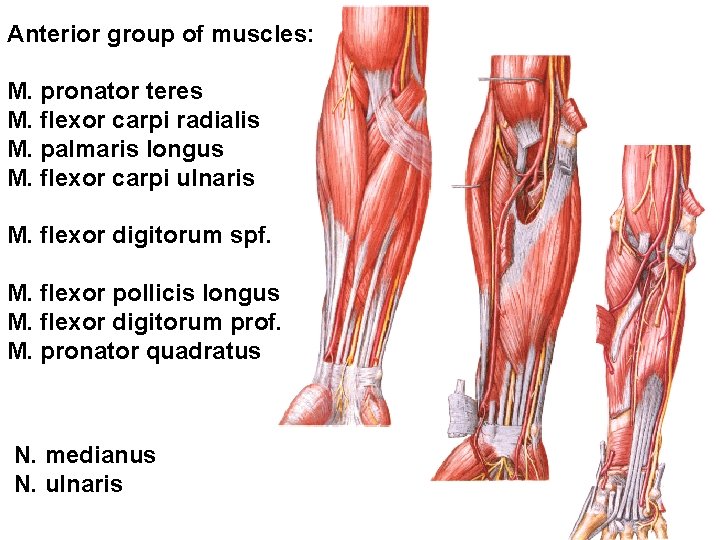

Anterior group of muscles: M. pronator teres M. flexor carpi radialis M. palmaris longus M. flexor carpi ulnaris M. flexor digitorum spf. M. flexor pollicis longus M. flexor digitorum prof. M. pronator quadratus N. medianus N. ulnaris